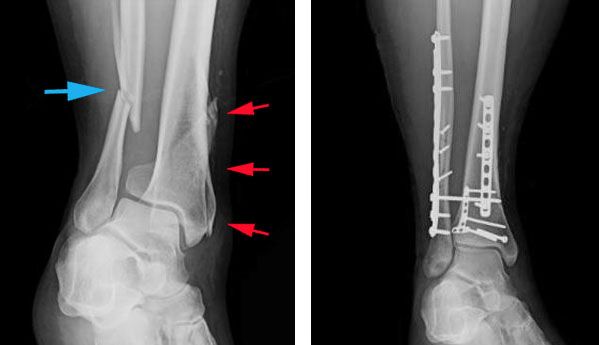

Plates and screws. During this operation, the bone fragments are first repositioned (reduced) into their normal alignment. They are held together with screws and metal plates attached to the outer surface of the bone.

Plates and screws are often used when intramedullary nailing may not be possible, such as for fractures that extend into either the knee or ankle joints.

X-rays of tibial shaft fracture and internal fixation

(Left) X-ray shows a fibula fracture (blue arrow) and a tibial shaft fracture (red arrows) that extends into the ankle joint. (Right) Both fractures have been treated with plates and screws.